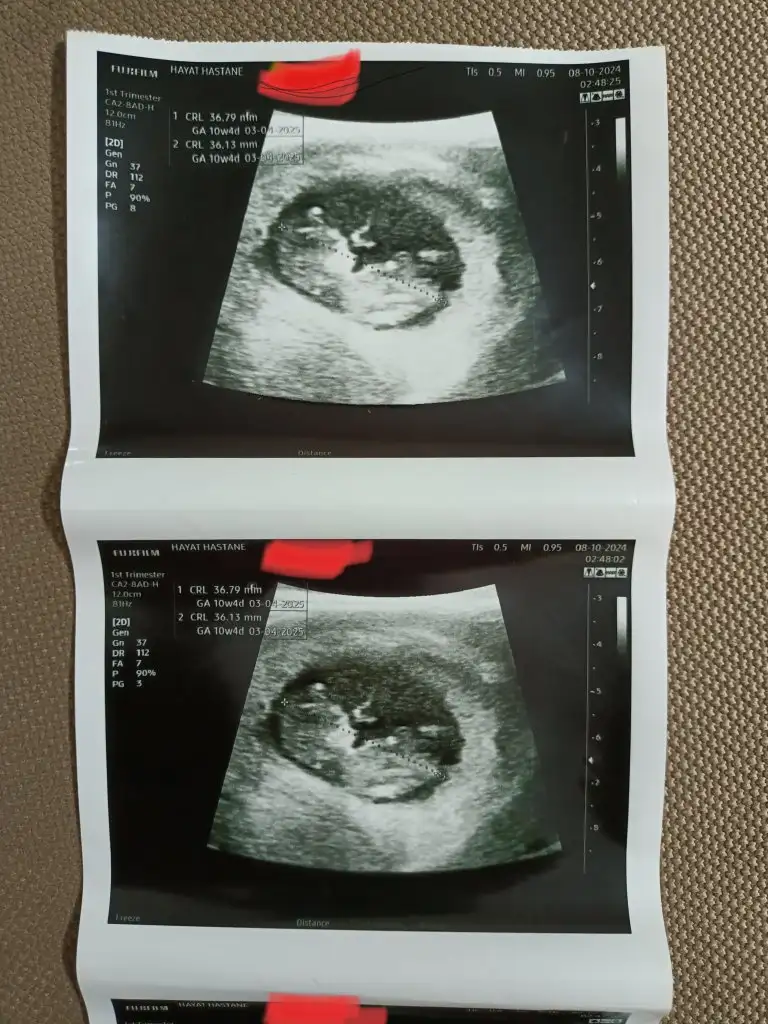

Merhaba, ben bebeğimi kaybettim.. 8 haftalıkken kalbi durdu. 9+5’te doktor muayenesine gittiğimde öğrendim. Öğrendiğimin ertesi günü de kürtaj oldum. Cinsiyetini hep çok merak ettim. Sürekli Çin, Rus, Maya takvimi vs bakıp duruyordum. En azından doğruluğu kesin olmasa bile, teoride bile olsa benim meleğim için de tahminde bulunabilir misiniz? Bu görüntü karından ultrason ve 6+4’teyken çekilmişti. Rabbim bebek bekleyen herkesin sağlıkla kucağına almasını nasip etsin.

Eklentiler

• IMG_6244.webp

IMG_6244.webp

7,1 KB · Görüntüleme: 53